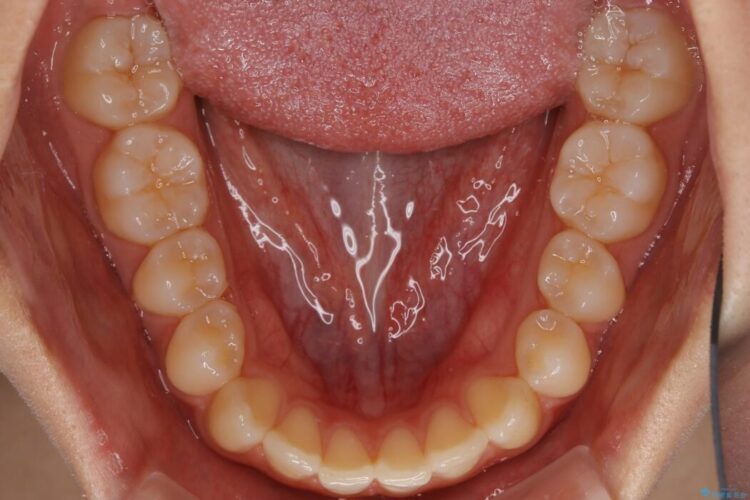

すきっ歯を改善したいとご来院された患者様です。

インビザライン・クリンチェック(シミュレーション)を行い、インビザラインライトで治せる範囲であると診断し、矯正治療を行いました。

マウスピース14枚・期間4ヶ月で主訴であるすきっ歯を改善し、治療を終えることが出来ました。